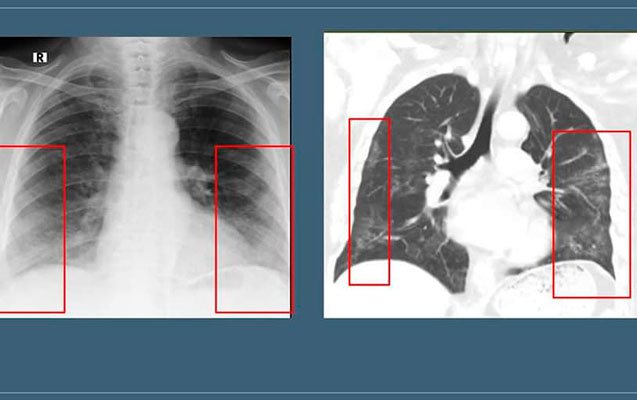

Hazırda “buzlu şüşə” görüntüsü koronavirus pnevmoniyasının əsas radiodiaqnostik əlaməti hesab edilir. Bu ,o deməkdir ki, normalda şəffaf havalı görünən ağciyərdə belə hallarda yarımşəffaf zonalar izlənilir, ağciyər sanki dumanlı görünür:

“Bu zaman bronx strukturlarının və pulmonar damarların saxlanması ilə ağciyərlərin eksudat və ya transudatla tutulması, interstisial qalınlaşmalar və ağciyər alveollarının hissəvi kollapsı ilə müşahidə olunan görüntü meydana çıxır. “Buzlu şüşə” xəstəliyin 3-4 günlərindən inkişaf etməyə başlayır və xəstə sağaldıqdan hətta bir ay sonra belə qala bilir. Xəstəliyin yüngül və orta ağır dərəcəsini keçirmiş xəstələrdə 2-3 aydan sonra dəyişikliklər tamamilə itir”.

Qeyd edək ki, “buzlu şüşə” görüntüsü döş qəfəsinin rentgenoqrafiya və KT müayinələrində aşkar edilir. Lakin bu məsələdə rentgenoqrafiya müayinəsinin həssaslığı aşağıdır. Ona görə də yoluxmanın ilk 1-4 günlərində rentgenoqram 25% hallarda tam normal ola bilər. Bu, pnevmoniyanın olmaması demək deyil. “Buzlu şüşə”nin KT müayinəsində görülməsi daha spesifikdir (Şəkildə eyni xəstənin rentgenoqrafiya və KT müayinələrində buzlu şüşə görüntüsünün təsviri verilib).